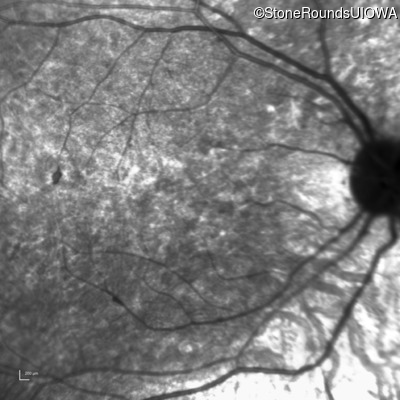

Infrared Fundus Photograph - Left - 5/200

Exemplar